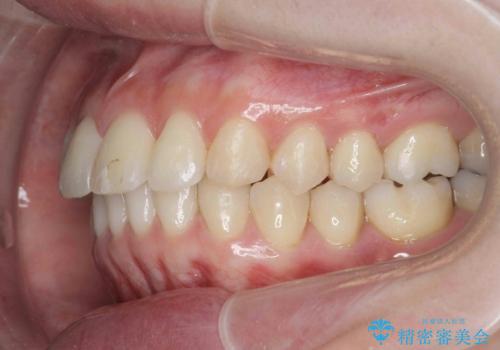

カリエール・マイクロインプラントを併用した歯の突出を改善する大きな遠心移動

- 口が閉じづらく、突出し歯が出っ歯に見えてしまうことの改善を求めて来院されました。

通常このような場合、抜歯してのワイヤー矯正治療も選択肢に入りますが、患者様の強い希望により抜歯を行わずマウスピースによる治療を選択しました。

カリエール・マイクロインプラントを用い、時間はかかりましたが大きく歯の後方移動が達成され、前歯の見た目が大きく改善されました。